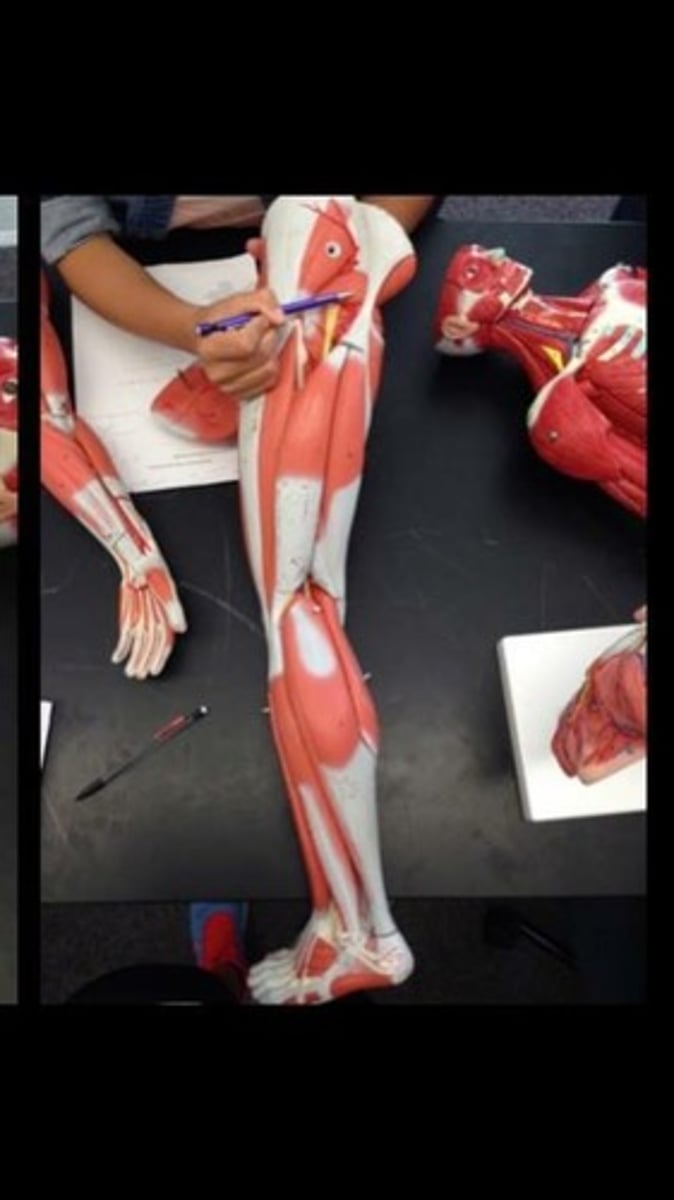

Skeletal muscle terms and structure

114 Terms

Rectus femoris

Vastus lateralis

Vastus intermedius

Vastus medialis

Sartorius

Fibularis brevis

Tibialis anterior

Extensor digitorum longus

Gastrocnemius lateral head

Gastrocnemius medial head

Flexor digitorum longus

Fibularis longus

Soleus

Flexor hallucis longus

Extensor digitorum brevis of foot